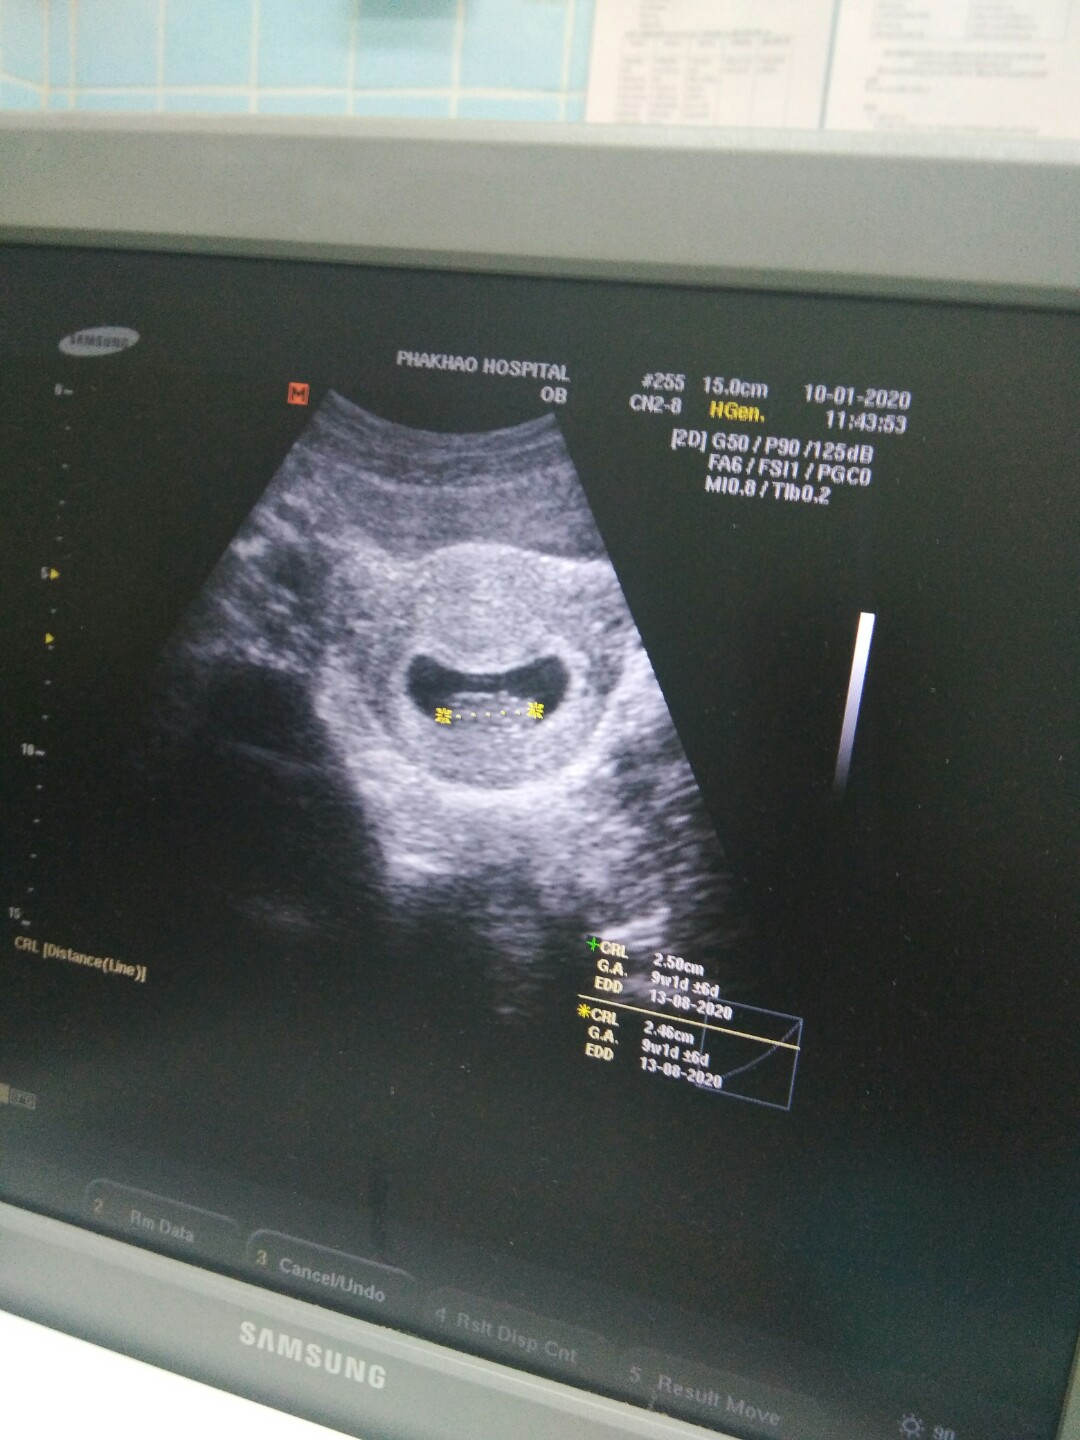

พรุ่งนี้9วีคค่ะ